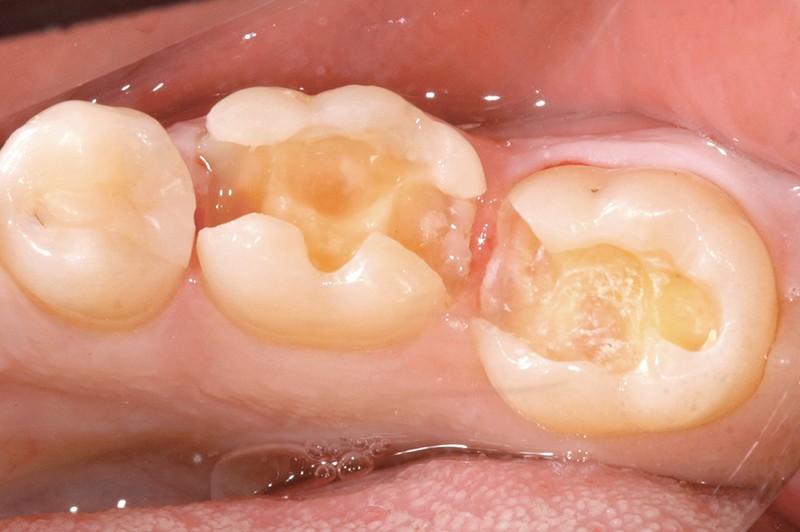

L’estimation de l’état pulpaire et de son potentiel réparateur sont des préalables fondamentaux avant tout traitement restaurateur de l’organe dentaire. Cependant, l’étroitesse du volume pulpaire enfermé dans une masse minérale rend l’évaluation directe du système vasculaire pulpaire délicate. Cet article porte sur l’analyse des critères décisisionnels cliniques et les tests pulpaires disponibles pour déterminer dans quel cas et comment la vitalité pulpaire peut être conservée ou si l’on doit procéder à la dépulpation. La prise en compte des processus de cicatrisation dentinaire ainsi que les délais et l’adoption de procédures opératoires restauratrices adaptées permettent d’assurer la préservation durable de la vitalité pulpaire dans les situations cliniques idoines.

L’estimation de l’état de santé de la pulpe et l’évaluation du pronostic pulpaire constituent des préalables indispensables à la mise en œuvre des restaurations sur les dents pulpées.

L’abandon des principes mécanistes de Black au profit d’une dentisterie a minima basée sur la préservation tissulaire couplée aux progrès des matériaux adhésifs et l’avènement de biomatériaux permettent aujourd’hui d’envisager, dans un grand nombre de situations cliniques, de conserver la dent pulpée et d’assurer le succès thérapeutique de nos restaurations. Encore faut-il procéder initialement à une évaluation de l’état pulpaire.

À ce titre, la problématique posée fréquemment avant de restaurer des dents pulpées se résume très souvent à savoir si la dent peut être conservée vivante ou si l’on doit procéder à sa dépulpation.

Mais, plus que l’état pulpaire initial, il s’agit de connaître le potentiel réparateur pulpaire de l’organe dentaire à traiter et d’en activer, le cas échéant, les mécanismes d’action.